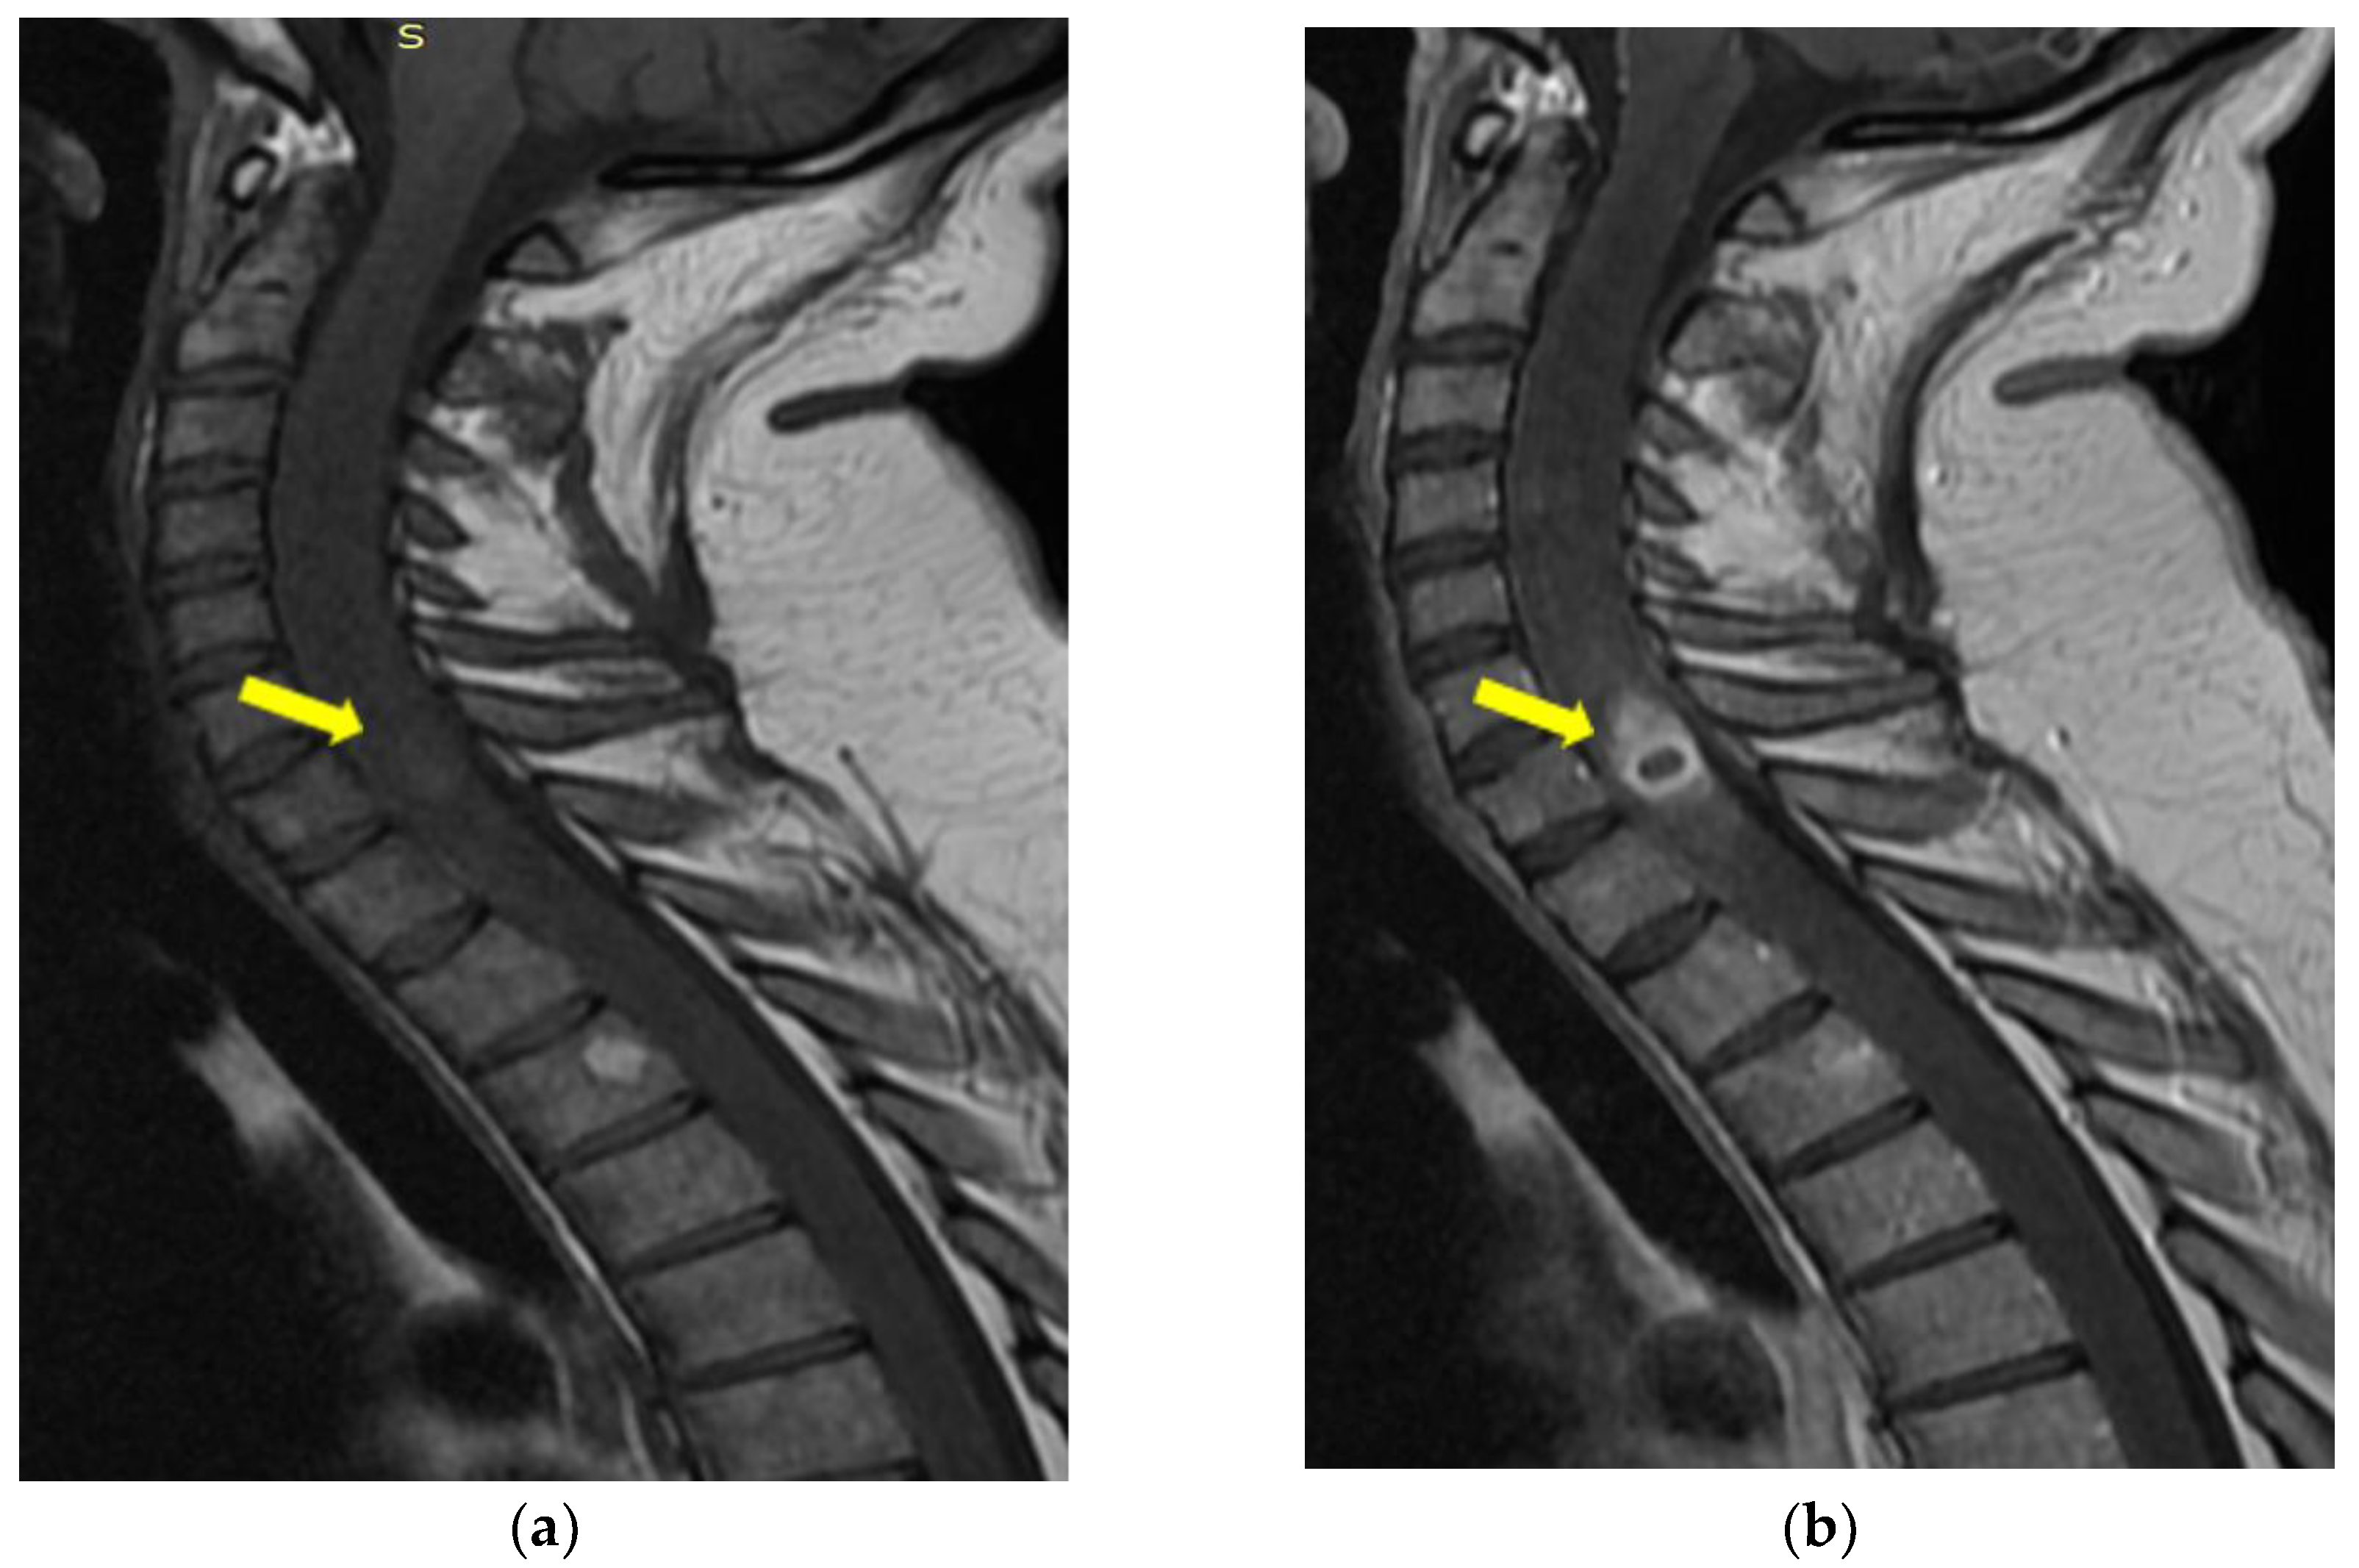

Cervico-Dorsal Intramedullary Spinal Cord Abscess with Aspergillus fumigates following Pulmonary Infection in an Immunocompetent Patient

2. Detailed Case Description

- Mycological demonstration of Aspergillus fumigates hyphae by microscopy from spu-tum, microscopy and culture from bronchial aspirate, and histopathological evi-dence of the presence of Aspergillus fumigates hyphae with dichotomous branching in the spinal cord biopsy;